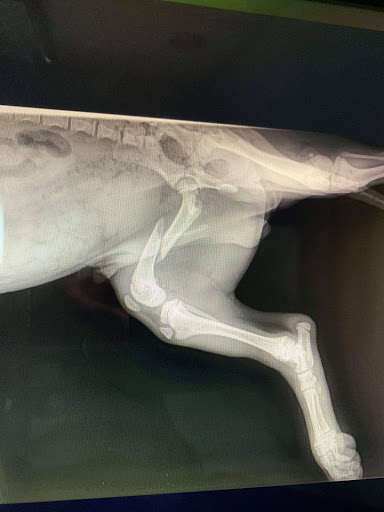

Huh. Sorry to hear about the bad experience with Dr. Whetstone, cause I came on here to say shes my new vet. I liked my old vet, but she (Dr. Whetstone) was so much better. My hamster fractured her leg last night (fell from one foot up; shes an elderly dwarf hamster), and my usual vet wasnt in on Saturdays. So I got referred to another place, which also didnt have their exotic pet vet in, so I finally got referred to this place. I was a walk-in. Loads of dogs, cats, bunnies, birds waiting their turn to be seen. Dr. Whetstone was able to see my hamster in under half an hour. She did a thorough examination of her, and didnt even have to scruff her to do so. And my hamster cooperated fairly well. Normally she screams bloody murder when she gets scruffed. The Doc showed me how my hamsters tibia was fully fractured. She was able to fasten a tiny splint on her even (under some general anesthesia gas). And its supposedly hard to put such a small animal under anesthesia, but she was able to do it with no problems. And my hamster recovered quickly. Dr. Whetstone even noticed the little details like her ears having crud in them, so she gave me something for that. And she checked out her teeth and showed me why my hamster has been having such a hard time chewing lately. I already knew my hamster has a tumor on her belly, but she said it really felt like a benign tumor. My last vet said he could only guess. Then again, that was a month ago, maybe the tumor has only recently developed to the point of being able to tell. Either way, Dr. Whetstone was able to really put me at ease. Took care of everything. Even gave me the teeth trimming and the splint for free since I was already paying for anesthesia. The check-up was $53, the anesthesia procedure $40, and the Baytril was $11. Felt I really got my moneys worth relative to other vet visits at other places. And seems like everyone (staff) there that I met really gave a darn about animals of all sizes.